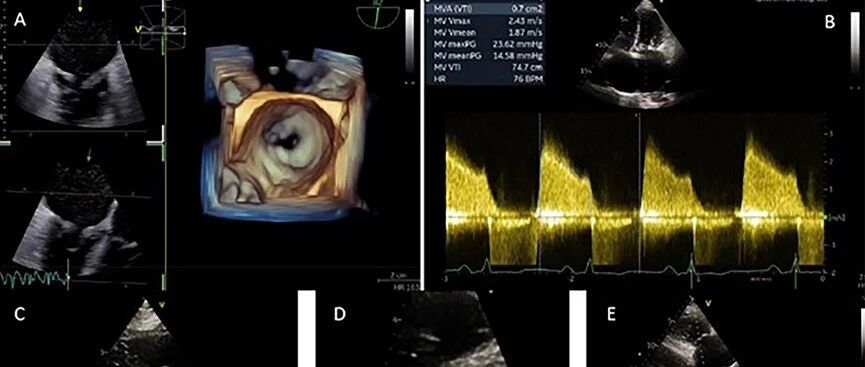

病例 | 高危孕妇重度钙化性二尖瓣狭窄,拒绝终止妊娠且不宜外科手术,介入团队如何破局? 心在线 · 公众号 · · 3 月前 · |